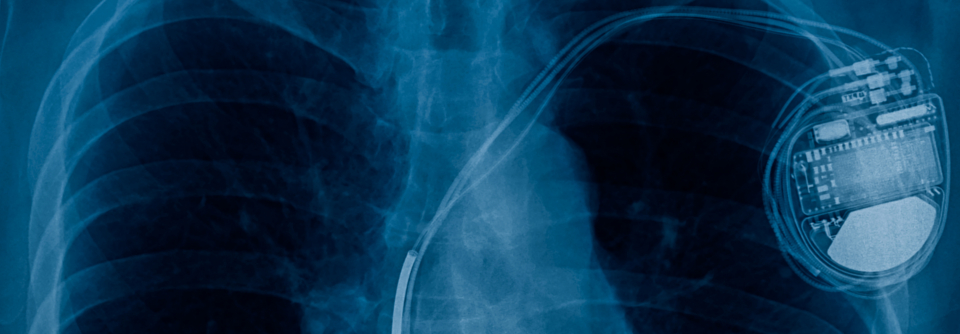

Im zweijährigen Follow-up kam es bei 2 % der Behandelten zu einer Entzündung, deviceassoziierte Todesfälle traten nicht auf. Im zweijährigen Follow-up kam es bei 2 % der Behandelten zu einer Entzündung, deviceassoziierte Todesfälle traten nicht auf. © iStock/Jan-Otto

Industrieländer unterstützen Ärzte und Patienten in ärmeren Regionen mit resterilisierten Schrittmacher und Defibrillatoren. Bei der Wiederverwendung gibt es nach wie vor Bedenken bezüglich des deviceassoziierten Infektionsrisikos. Das aber scheint nicht höher zu sein als nach der Implantation neuer Geräte.